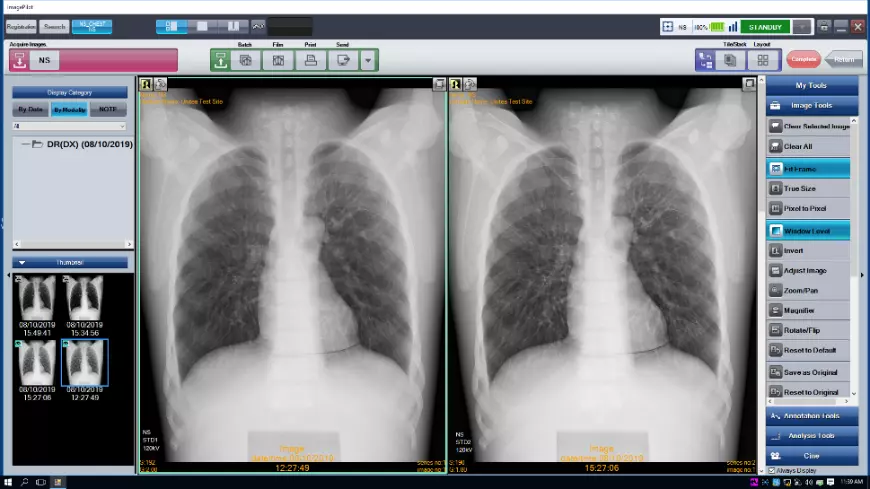

- ImagePilot: Всё в одном

Регистрация + Получение снимка + Просмотр + Измерения + miniPACS

ImagePilot: Всё в одном Простая регистрация пациента, быстрый просмотр и описание, множество инструментов для измерений и обработки снимков, мини-PACS для хранения данных, различные опции вывода и печати